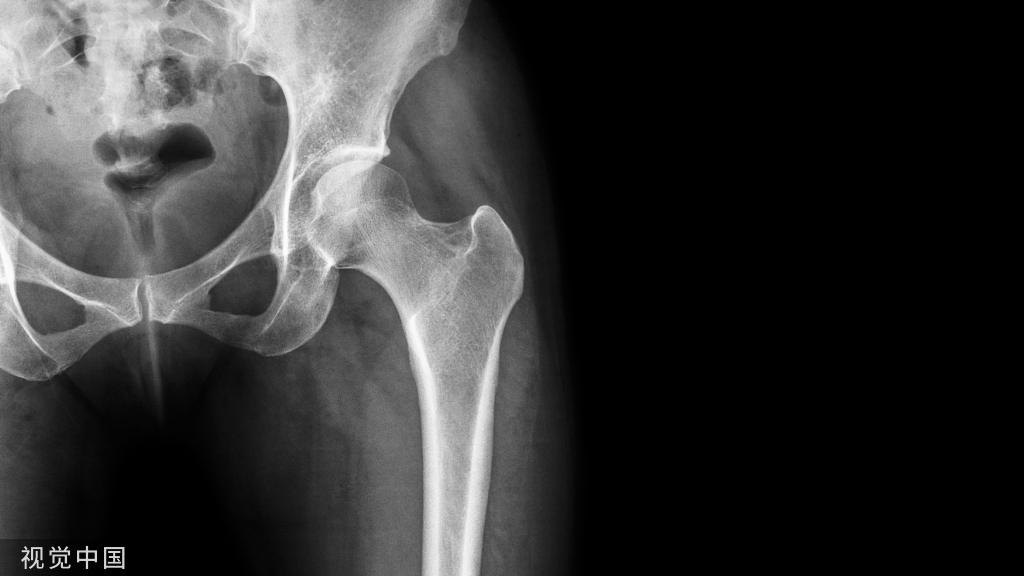

年轻人骨折后骨密度降低可以恢复到原来水平,老年人骨质疏松骨折后的骨密度下降恢复不到原来水平,所以容易造成二次骨折。

急性骨吸收

关节制动附近的急性骨吸收、制动后影响骨传导、骨愈合

24岁因故骨折50天没有负重,出现严重的骨质疏松。